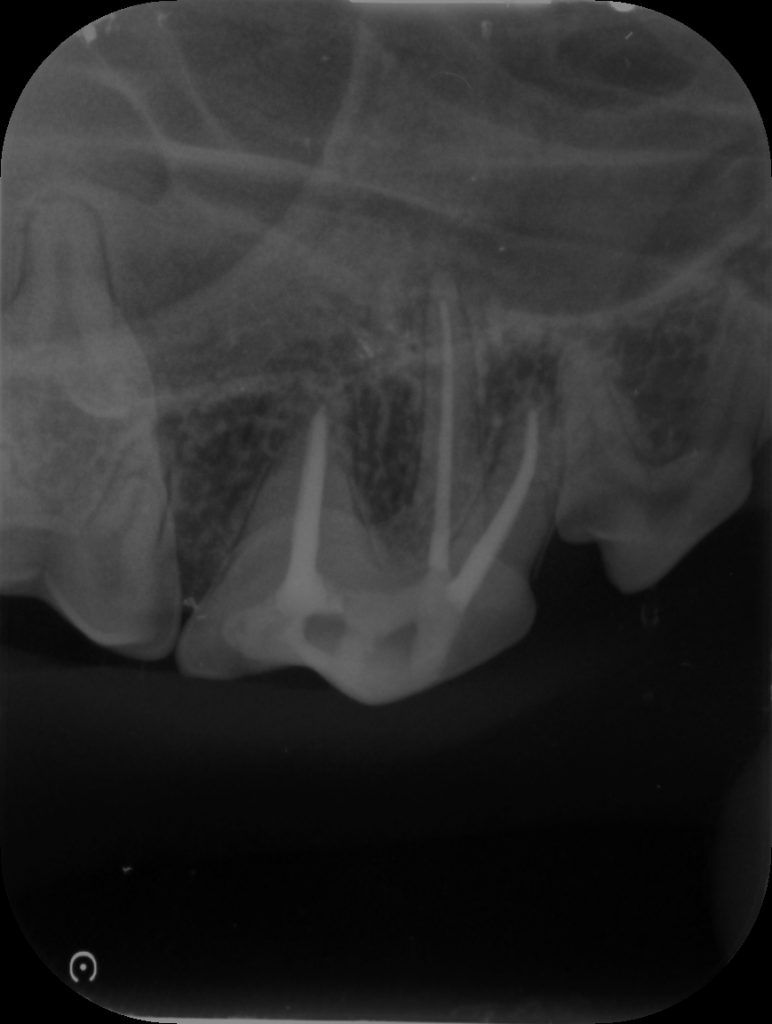

この子もレントゲンを撮影すると

わかりにくいと思いますが、このような範囲で骨が溶けている変化が見られます。

処置が終わるとこのように神経のあった管に白いものが詰まっている状態になっています。これにより汚いものが根っこの先から出ないようにできます。

レントゲンではまだ以前の骨の変化は残っていましたが根尖周囲の骨が白さを増している状態でしたので今のところ悪化はないと判断できます。